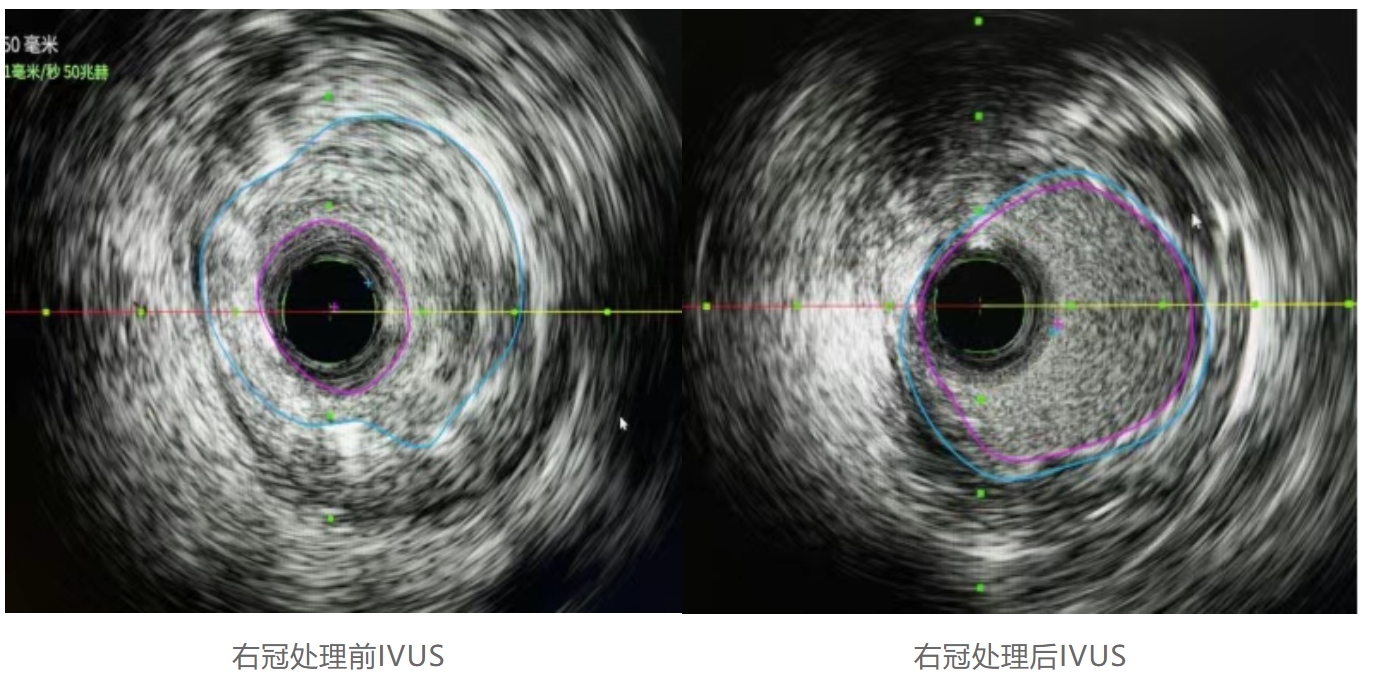

右冠处理情况:右冠处理前IVUS提示斑块负荷75%,管腔面积1.93mm²,经准分子激光斑块消蚀术处理后斑块负荷19%,管腔面积6.55mm²。